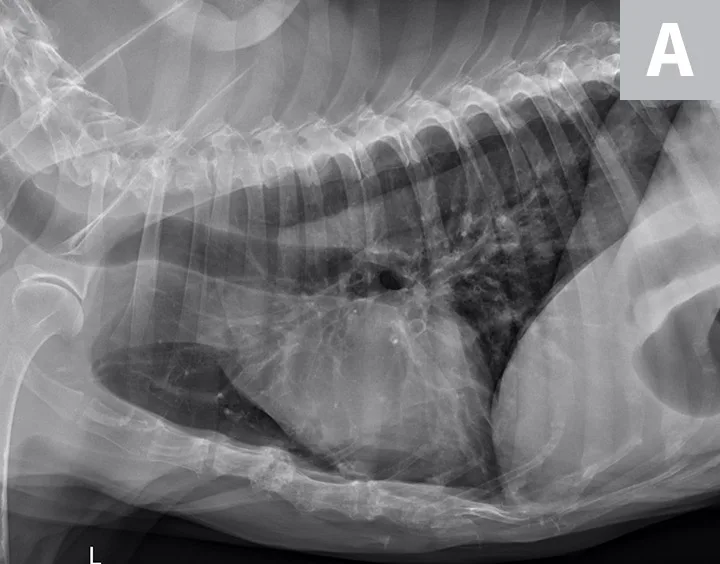

Serum chemistry profile and CBC results were normal, and heartworm antigen test results were negative. Thoracic radiography (right lateral, left lateral, ventrodorsal) revealed a diffuse bronchial pattern but was otherwise unremarkable with no cardiomegaly (vertebral left atrial size, 2.1 [normal, 1.4-2.2]; vertebral heart scale, 9 [normal, 8.7-10.7]) or observable airway collapse (Figure 1). Arterial blood gas showed partial pressure of arterial oxygen 97 mm Hg (normal, 81-103 mm Hg). Echocardiography revealed myxomatous mitral valve degeneration (B1) with no evidence of pulmonary hypertension.2 Laryngoscopy/bronchoscopy showed moderate mucosal irregularity and increased mucus of the lobar bronchi (Figure 2) with normal laryngeal function. Concurrent dynamic bronchial collapse of the left and right mainstem bronchi (grade II/III) was observed (Figure 3).3 Bronchoalveolar lavage was performed and submitted for cytologic evaluation and aerobic culture. Cytology revealed nonseptic neutrophilic inflammation (Figure 4); aerobic culture was negative.

FIGURE 1A

Thickening and mineralization of the airways characteristic of a bronchial pattern and suggestive of chronic airway inflammation